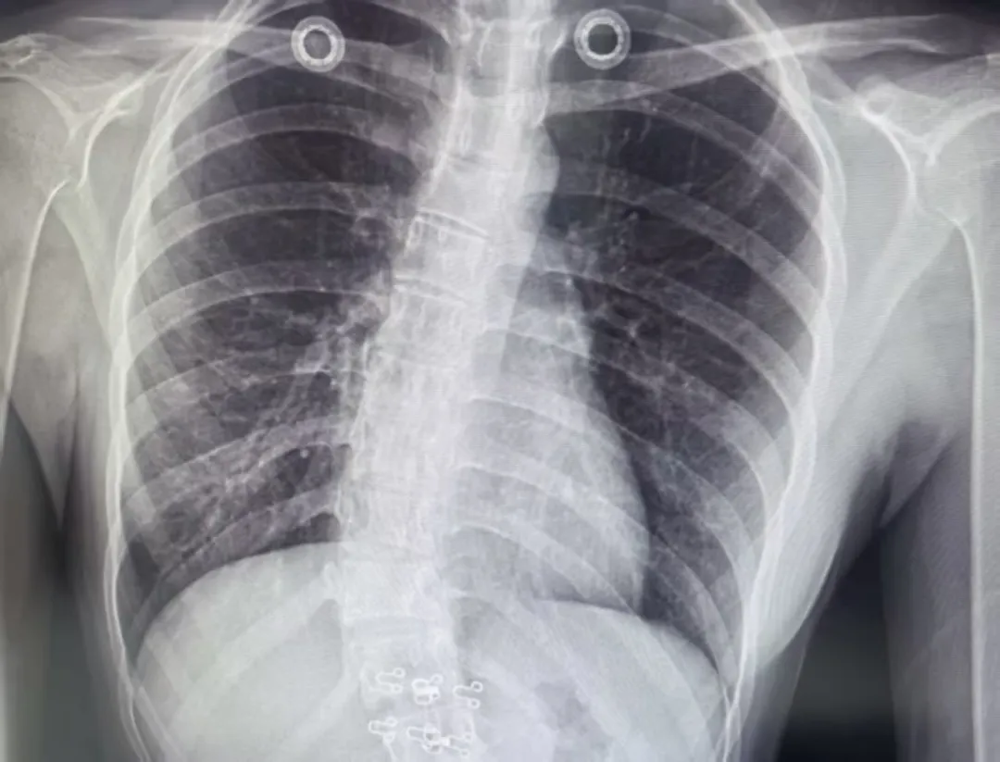

只要发现以上任何一种异常,务必立即带孩子到医院脊柱外科做专业脊柱X光检查,明确侧弯角度,切勿抱有“长大就好了”的侥幸心理。

脊柱是人体最大的支撑,正常情况下,脊柱有4个弯曲,从正面看是直的,侧面看是S形。而脊柱侧凸,俗称脊柱侧弯,是脊柱弯曲异常并伴椎体旋转的三维脊柱畸形,常采用Cobb法测量弯曲角度,大于10°即可确诊。

针对青少年特发性脊柱侧弯的治疗分非手术治疗和手术治疗。非手术治疗主要适用于轻中度脊柱侧弯患者,这部分人群占较高比例,是目前预防和治疗脊柱侧弯不可或缺的方式,包括各类不良姿势纠正、生活习惯调整、特异性运动疗法、旋转成角呼吸训练和支具治疗等。治疗建议:

Cobb角小于5°~10°的患者建议定期观察随访,年度复查一次脊柱X光片;

Cobb角为10°~20°的患者建议接受系统的脊柱姿势评估和各类特异性运动训练,且每隔6个月复查一次脊柱X光片;

Cobb角为20°~40°的患者建议接受系统的脊柱姿势评估、支具治疗和各类特异性运动训练。同时结合骨骼成熟度和侧凸进展状况,合理调整临床和/或影像学随访频率。

Cobb角>40°的患者需要考虑通过手术的方法进行干预。